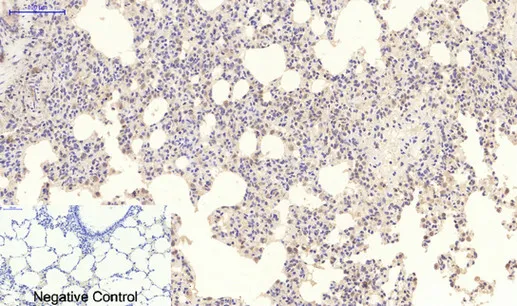

LC3A(5G10)Mouse Monoclonal Antibody

Cat: AMM13240

Size1:50μL Price1:$118

Size2:100μL Price2:$220

Size3:200μL Price3:$380

Application:WB,IF-P,IF-F,ICC/IF,IHC-P

Reactivity:Human,Rat,Mouse

Conjugate:Unconjugated

Optional conjugates: Biotin, FITC (free of charge). See other 26 conjugates.

Gene Name:MAP1LC3A